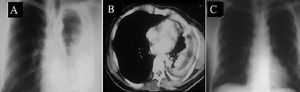

A. Chronic empyema. Note the thickness and fibrotic nature of the pleural cortex. B. Purulent material has been removed and the visceral pleural cortex can be observed on the bottom, where it restricts lung expansion. C. The lung has been completely decorticated and there is no residual dead space

The surgical protocol consisted of double lumen intubation and placement of an epidural catheter for analgesia. The surgical approach was orientated by imaging study findings using limited incision or postero-lateral thoracotomies; the latter were used for large or loculated empyemas. Surgery included evacuation of all purulent material and formal decortication with the aim of obtaining the largest possible pulmonary expansion. In most cases, decortication of parietal pleura was partial and performed in accordance with the need for complete decortication of the visceral pleura. The diaphragm was routinely separated from the lung and from adhesions to promote as much obliteration of the empyema cavity as possible (Figure 1). Two chest tubes were inserted at the end of the operation. No pleural irrigation or fibrin sealant was used in any case.3,4,8 Patients were extubated in the operating room and sent to the ward for postoperative management. Patients were managed in the intensive care unit only when mechanical ventilation or vasopressors were required. Aggressive respiratory therapy was performed. Chest tubes were removed when there was no air leakage and when the drainage was less than 50 to 100 ml per day. Follow-up took place in the outpatient clinic and when needed, patients and primary physicians were contacted by phone.

In our cases, pleural fluid cultures showed bacterial growth in 36.4% of patients, which is comparable to several previous reports.5,8–10 Additionally, lactic dehydrogenase was consistently elevated with an average value of 6133.8 UI/L. Soriano et al.16 established a direct relationship between higher levels of lactic dehydrogenase and a longer disease duration. Imaging studies consisted of chest roentgenograms, ultrasound and chest CT. These studies demonstrated a thick pleural cortex and constriction of the thoracic cage. Chest CT was particularly useful for showing the pleural cortex, loculations, size of the empyema and evidence of constriction of the thoracic cage. There are no specific indicators to confirm the chronicity of the empyemas;20 however, in this series, the presence of the pleural cortex and constriction of the thoracic cage (Figure 2) coupled with evolution times of more than 15 days was indicative of chronic empyema in all cases. During surgery, reduction of the intercostal spaces and the fibrous pleural cortex were evident; these are features of chronic empyema. In addition to showing the characteristics of the empyemas, chest CT allows the surgeon to locate and determine the best surgical approach, either limited or postero-lateral thoracotomy. Since 1996, we have routinely performed chest CT before surgery for all patients diagnosed with empyema.

A. Chest roentgenogram shows a large left empyema. B. Computed tomography of the chest showing significant restriction of the thoracic cage and thick pleural cortex. C. Postoperative chest roentgenogram with excellent pulmonary expansion (Incidentally, partial removal of a rib can be seen; this was the only patient that required such a procedure)